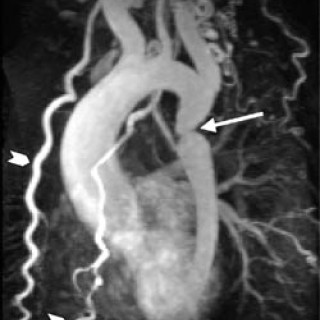

Bildediagnostikk spiller en stor rolle i mange kliniske disipliner, så også i kardiologien. Røntgen thorax, ekkokardiografi med doppler, nukleærmedisinske metoder, invasiv kateterbasert angiografi, MR (magnetisk resonanstomografi, magnettomografi) og i den siste tid også multidetektor-CT er alle metoder som spiller viktige, men ulike roller innen diagnostikk av hjertesykdommer. Metodene har sine sterke og svake sider, dels på grunn av apparaturens tekniske muligheter, dels på grunn av pris, kompetanse og tilgjengelighet. Hensikten med denne artikkelen er å plassere MR i kardiologiens...